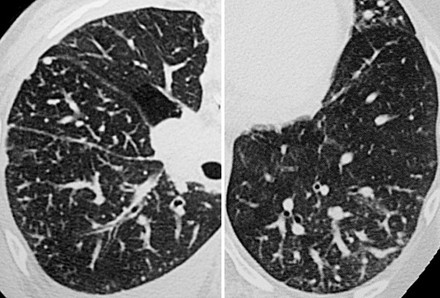

DDx for Tree - in - Bud

Tree in Bud Infective bronchiolitis:

INFECTIVE BRONCHIOLITIS

• Mycobacterium: TB; Mycobacterium Avium Complex (MAC)

• Viral pneunomia

• Fungal pneumonia,

• ABPA

• Pneumocystis pneumonia (PCP)

BRONCHIECTASIS

• Cystic Fibrosis

• Immotile Cilia Syndrome (Kartagener Syndrome)

Rare: NEOPLASM:

• Bronchioalveolar Carcinoma

• Pulmonary lymphoma